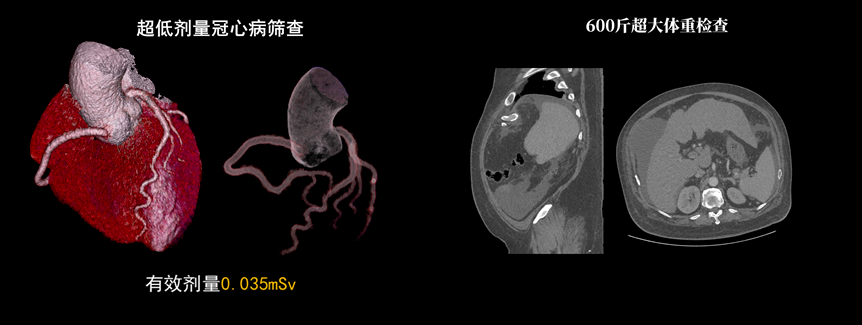

該設(shè)備除具備普通CT的功能外,還具備速度快、精度高、智能化、高效能、微劑量、大孔徑等優(yōu)勢(shì)。16厘米Z軸探測(cè)器、23毫秒時(shí)間分辨率,聯(lián)影天河640CT讓冠脈CTA檢查擁有“不選擇”的權(quán)利。搭載的一站式聯(lián)合掃描技術(shù),輔以便捷高效的后處理功能,AI精準(zhǔn)血管分割,自動(dòng)預(yù)處理加載,逐支血管觀察,全時(shí)提效,可實(shí)現(xiàn)一次注射造影劑獲取多部位CTA、CTP和4D動(dòng)態(tài)圖像,不僅可以助力腦卒中解決方案,還可助力腦血管畸形、腦動(dòng)脈瘤等其他腦血管病的結(jié)構(gòu)和功能評(píng)估。

液態(tài)金屬軸承球管,陽極直冷技術(shù),提供30MHU球管熱容量,可高通量連續(xù)掃描。AI劑量調(diào)制、迭代重建等復(fù)合劑量控制方案,為體檢患者提供優(yōu)化劑量掃查。82cm大孔徑,讓大體型患者檢查更加舒適。

天河640CT的寬體探測(cè)器單圈掃描即可覆蓋全心臟,搭配快速機(jī)架轉(zhuǎn)速和獨(dú)家AI冠脈追焦技術(shù),可實(shí)現(xiàn)單心動(dòng)周期內(nèi)無限心率、無限心律的冠脈成像,對(duì)于嚴(yán)重心律不齊、房顫、房撲,超高心率等情況,天河640CT都能在單心動(dòng)周期內(nèi)獲得優(yōu)質(zhì)圖像。